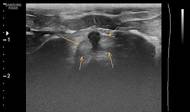

Bezděková Z. Hlavnička u skotu – case report. Veterinářství 2026;76(1):29-32. SOUHRNČlánek popisuje klinický případ výskytu hlavničky u červenostrakatého skotu. Hlavnička skotu nebo také maligní katarální horečka se vyskytuje po celém světě a v České republice jsou spíše raritní záchyty. Kazuistika se týká plemene červenostrakatého skotu. Klinické příznaky byly nespecifické a…